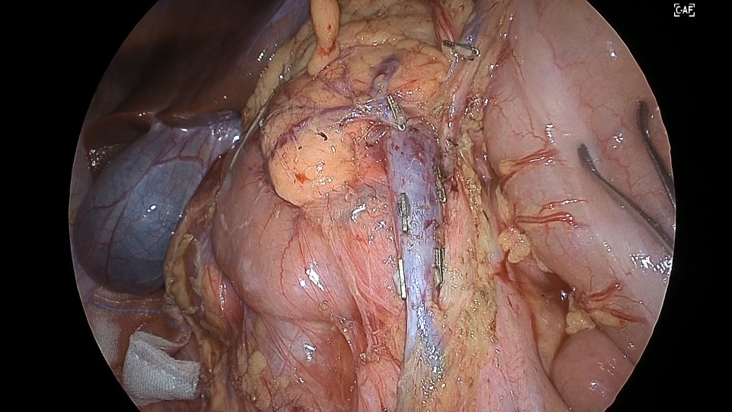

バックライトはパネルの背面全体に配置されており、これらの細やかなコントロールを可能にしたものがローカルディミング機能です。このバックライトの部分制御により、従来のモニターであれば表現が難しかった暗部の色味を入力された映像通りに表現することができるようになりました。これにより、遠点の暗い部分の映像や出血部分の色の違いも従来のモニターよりも見やすく表現することができます。暗い部分でも見やすく、明るい部分でも白飛びしないようにしたことで、HDRに適した表現が可能になりました。